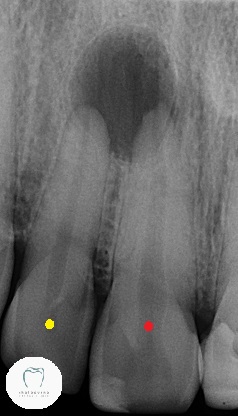

Both teeth are badly discoloured and heavily filled. His upper right central (red dot) tooth was hurting. A lot. If we tapped on it, there was even more pain. So we took an X-ray and found this:

You can see the great big black circle above and around the roots of two teeth. That’s an abscess. Now the question becomes “One tooth or two?” Looking at this X-ray, I’d say two teeth are compromised.

Yet when we put something very cold on the two teeth, the next door lateral tooth (Yellow dot) could feel it. The prime suspect, the central incisor with the red dot, most certainly could not feel the cold! So there’s some chance the nerve can be kept alive in one tooth.